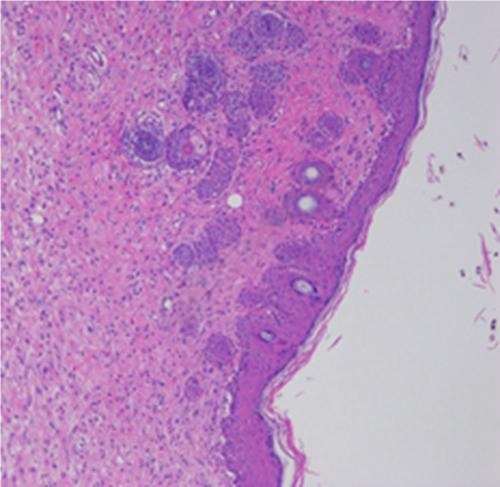

2.大鼠皮肤损伤HE